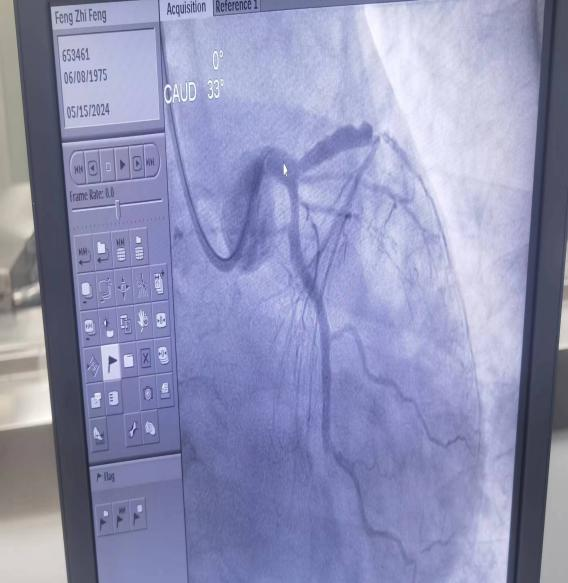

放置架开通血管后